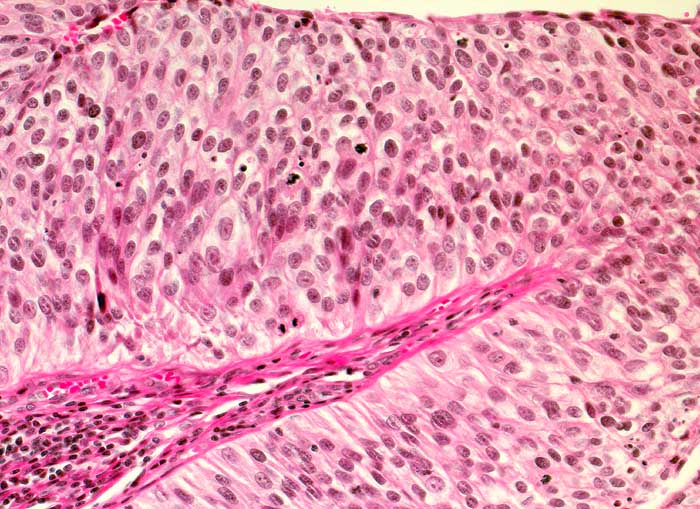

n/ Papilläres Urothelkarzinom pTa, G1 + G2

Papilläres Urothelkarzinom pTa, G1 + G2

Bei den meisten papillären Urotheltumoren finden sich kleine Büschel von kubischen oder zylindrischen Urothelien. Die Kerne sind leicht vergrössert, oft spindelig und hyperchromatisch. Papilläre Karzinome mit leichter Epitheldysplasie sind aufgrund der sehr geringen Zellatypien in bis zu 50% der Fälle zytologisch nicht diagnostizierbar. Bei mässiger Epitheldysplasie sind die Urothelien polymorpher und hyperchromatischer.

Unten werden Beispiele von einem hoch differenzierten und drei mässig differenzierten papillären Karzinomen gezeigt.